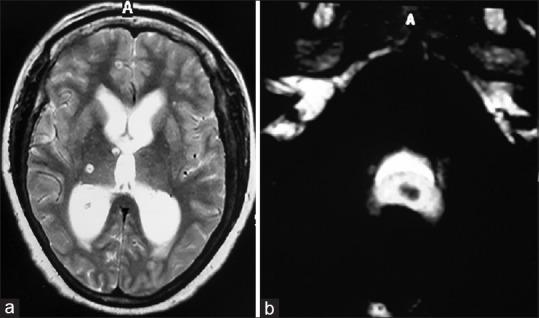

对2010年至2018年间接受内镜治疗的26例IVNCC患者的临床记录和随访进行回顾性分析。IVNCC的诊断基于脑部增强磁共振成像。通过额部钻孔进行0°内镜经颅内镜检查。进行第三脑室造瘘术并用血管导管切除囊尾蚴囊肿。

结果

第三脑室内囊肿的脑室内囊肿切除成功率,无论是完全切除还是部分切除,均为100%(14/14);第四脑室内囊肿为62.5%(5/8);侧脑室内囊肿为100%(4/4)。内镜下囊肿切除的总体成功率为88.46%。88.46%的病例成功建立了CSF流动通路。平均随访时间为44个月,所有患者在随访期间均无症状。